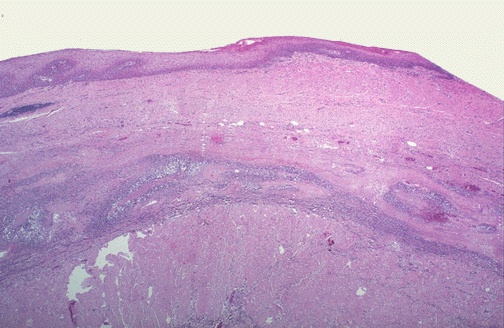

Below the squamous mucosa is an elongated, inflamed varix. Variceal bleeding can be massive and difficult to control.